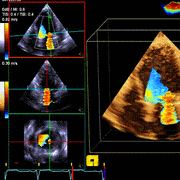

心电图(Electrocardiogram,ECG或者EKG)是利用心电图机从体表记录心脏每一心动周期所产生的电活动变化图形的技术。心电图是测量和诊断异常心脏节律的最好的方法,其是诊断心电传导组织... 当前位置: 疾病库首页心电图 心电图如有就诊需求,点击预约挂号填写信息,以便我们能及时与您联系 预约挂号广告 什么是心电图?心电图(Electr...